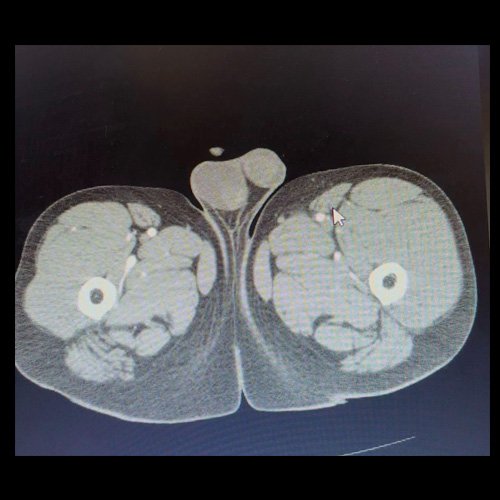

• AngioTAC de miembros inferiores (Día 0): Ateromatosis parietal calcificada parcheada en todo el territorio aorto-ilíaco-femoral bilateral. LADO DERECHO: Arteria ilíaca interna: de calibre y trayecto conservado, permeable. Arterias ilíaca externa y femoral común: de calibre y trayecto conservados, permeables. Arterias circunfleja ilíaca superficial y epigástrica superficial: de calibre y trayecto conservados, permeables. Arteria femoral superficial: de calibre y trayecto conservado, permeable. Arteria femoral profunda: de calibre y trayecto conservado, permeable. Arterias circunflejas femoral medial y lateral: de calibre y trayecto conservados, permeables. Arteria poplítea: de calibre y trayecto conservado, permeable. Arteria tibial anterior: de calibre y trayecto conservado, permeable. Arteria tibial posterior: de calibre y trayecto conservado, permeable. Cambios artrodegenerativos coxo-femorales y tricompartimentales en la rodilla. Signos de entesopatía cuadricipital distal. No se observan alteraciones a nivel de los grupos musculares visualizados. La disposición del tejido graso es normal. LADO IZQUIERDO: En fase angiográfica se observa menor calibre y opacificación de las arterias femoral superficial y profunda, poplítea y de sus ramas musculares en muslo y pierna en comparación con el miembro contralateral, con opacificación arterial preservada. En fase venosa se evidencia mayor la densidad endovascular de las mismas hasta el tercio distal de la pierna, donde se logran identificar a las arterias peronea, tibial anterior y tibial posterior. Se evidencia un defecto de relleno de la vena ilíaca común izquierda, en su nacimiento, en relación a trombosis venosa profunda. No se identifica compromiso de la porción visualizada de la vena cava inferior ni del sistema venoso ilíaco contralateral. Se visualiza aumento del tamaño de todos los grupos musculares del muslo izquierdo con respecto al contralateral y retardo de la concentración de contraste, asociado a edema de los tejidos blandos superficiales. Reticulación de la grasa de la región inguinal. Cambios artrodegenerativos coxo-femorales y tricompartimentales en la rodilla. Signos de entesopatía cuadricipital distal. No se observan alteraciones a nivel del fémur ni de las porciones visualizadas de la tibia y el peroné.

• AngioTAC de miembros inferiores (Día 2): Ateromatosis parietal calcificada parcheada en todo el territorio aorto-ilíaco-femoral bilateral. LADO DERECHO: Arteria ilíaca interna: de calibre y trayecto conservado, permeable. Arterias ilíaca externa y femoral común: de calibre y trayecto conservados, permeables. Arterias circunfleja ilíaca superficial y epigástrica superficial: de calibre y trayecto conservados, permeables. Arteria femoral superficial: de calibre y trayecto conservado, permeable. Arteria femoral profunda: de calibre y trayecto conservado, permeable. Arterias circunflejas femoral medial y lateral: de calibre y trayecto conservados, permeables. Arteria poplítea: de calibre y trayecto conservado, permeable. Arteria tibial anterior: de calibre y trayecto conservado, permeable. Arteria tibial posterior: de calibre y trayecto conservado, permeable. Vena ilíaca primitiva: 13 mm, vena ilíaca externa 11 mm, vena ilíaca interna 7 mm. LADO IZQUIERDO: En esta ocasión, en fase angiográfica se observa de calibre y opacificación conservada de las arterias femoral superficial y profunda, poplítea y de sus ramas musculares en muslo y pierna. En fase venosa se evidencia un defecto de relleno endoluminal de la vena primitiva izquierda que impresiona extenderse actualmente a la vena iliaca externa, a la vena femoral superficial y poplítea, hasta nivel del hueco homonimo, las cuales se visualizan aumentadas de calibre con respecto a sus contralaterales, en relación a trombosis venosa profunda. Se sugiere cotejar con ecodoppler de miembros inferiores. No se identifica compromiso de la porción visualizada de la vena cava inferior ni del sistema venoso ilíaco contralateral. Se visualiza dispositivo vascular en VCI (filtro VCI), infrayacente a las venas renales. Presenta aumento del diámetro del muslo izquierdo con respecto a su contralateral, asociado a edema de los tejidos blandos superficiales. Reticulación de la grasa de la región inguinal a predominio izquierdo con algunas burbujas aéreas. Se observa inmediatamente infrayacente a los antes mencionado, un área hiperdensa que realza en fase venosa, con centro hipodenso, que mide 2.2 cm x 1.4 cm, ya visualizado en tomografía previa. Cambios artrodegenerativos coxo-femorales y tricompartimentales en la rodilla. Signos de entesopatía cuadricipital distal. No se observan alteraciones a nivel del fémur ni de las porciones visualizadas de la tibia y el peroné. Arteria ilíaca interna: de calibre y trayecto conservado, permeable. Arterias ilíaca externa y femoral común: de calibre y trayecto conservados, permeables. Arterias circunfleja ilíaca superficial y epigástrica superficial: de calibre y trayecto conservados, permeables. Arteria femoral superficial: de calibre y trayecto conservado, permeable. Arteria femoral profunda: de calibre y trayecto conservado, permeable. Arterias circunflejas femoral medial y lateral: de calibre y trayecto conservados, permeables. Arteria poplítea, tibial anterior y tibial posterior: de calibre disminuido con respecto a su contralateral, permeables. Vena ilíaca primitiva: 14 mm, vena ilíaca externa 17 mm, vena ilíaca interna 9 mm. Calcificaciones en conducto inguinal bilateral. Hidrocele bilateral.

Angio TAC de miembros inferiores (Día 0)

Angio TAC de miembros inferiores (Día 2)